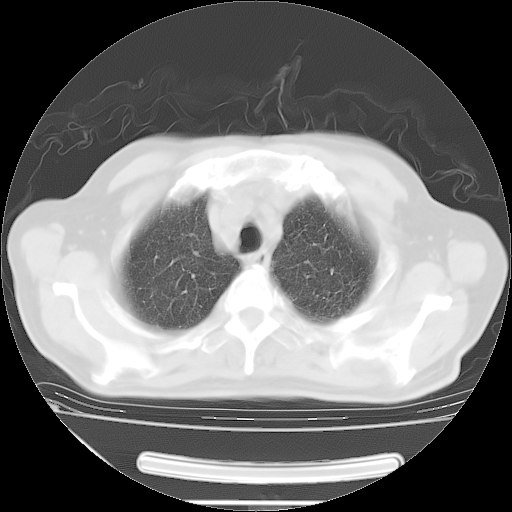

今天复查肺部CT,发现双肺广泛磨玻璃样改变。所以我把3月19日和5月9日相隔50天的肺部CT上传。请大家会诊。

2009年3月19日肺部CT片。

5月9日肺部CT(在4月27日齐鲁医院肺部CT描述部分肺组织磨玻璃样改变,12天后肺组织广泛磨玻璃样改变)

大致读了系列胸部CT:纵隔窗无明显异常,肺窗:从4、27至今:主要是双肺中下野外带可见毛玻璃样改变,目前处于急性肺泡炎阶段,至于原因考虑1、结替组织或胶原血管性疾病所致?2、恶性疾病如恶组在肺部所致的表现或细支气管肺泡癌?3、药物或其它原因如肺蛋白沉着症所致肺泡炎目前不太可能?总之,明天就去请我院的呼吸科、感染科、血液科和临免专家会诊哈。